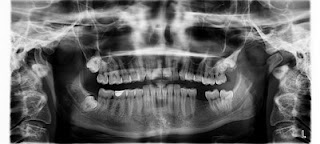

Открытие рентгеновского излучения является одним из самых важных

достижений человечества. Это настоящее чудо, которое позволяет сохранять зубы,

исправлять кости и обнаруживать многие заболевания.